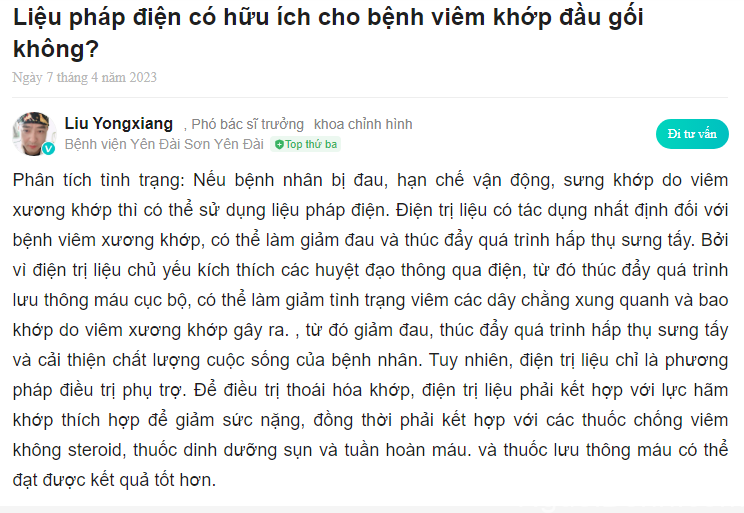

5.7. Chia sẻ từ Bác sĩ Liu Yongxiang và Bác sĩ Wang Xiaodong – Sử dụng liệu pháp điện cho bệnh viêm khớp gối

Các bác sĩ có uy tín đến từ những bệnh viện lớn đã giải đáp thắc mắc về đều trị bệnh viêm khớp gối bằng phươn pháp điện trị liệu:

Bác sĩ Liu Yongxiang – Phó trưởng khoa Phẫu thuật chỉnh hình, Bệnh viện Yên Đài:

Chia sẻ từ bác sĩ Liu Yongxiang (GG dịch tự động)

Bác sĩ Wang Xiaodong – Trưởng khoa Phẫu thuật chỉnh hình, Bệnh viện Đa khoa Đại học Y Thiên Tân:

Chia sẻ từ bác sĩ Wang Xiaodong (GG dịch tự động)